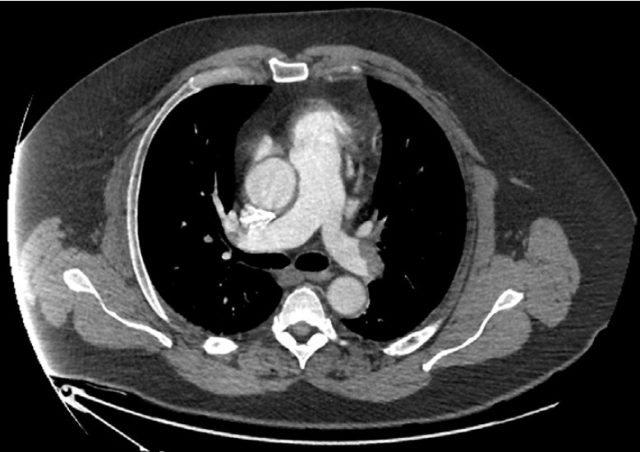

入院后,患者卒中量表评分(NIHSS)为 7 分,随即进行头部 CT 血管造影,显示患者左侧颞叶及岛叶缺血灶,确诊为缺血性脑卒中,并未发现动脉闭塞;肺动脉 CT 血管造影显示双侧肺动脉几乎全部闭塞(如图 1);下肢静脉彩超显示双侧 DVT;经颅多普勒彩超显示静息状态下有微栓子信号,当进行 Valsalva 动作(编者注:关闭口鼻后用力做呼气动作)时信号明显升高。

图 1:肺动脉 CT 血管造影显示双侧肺动脉几乎完全闭塞